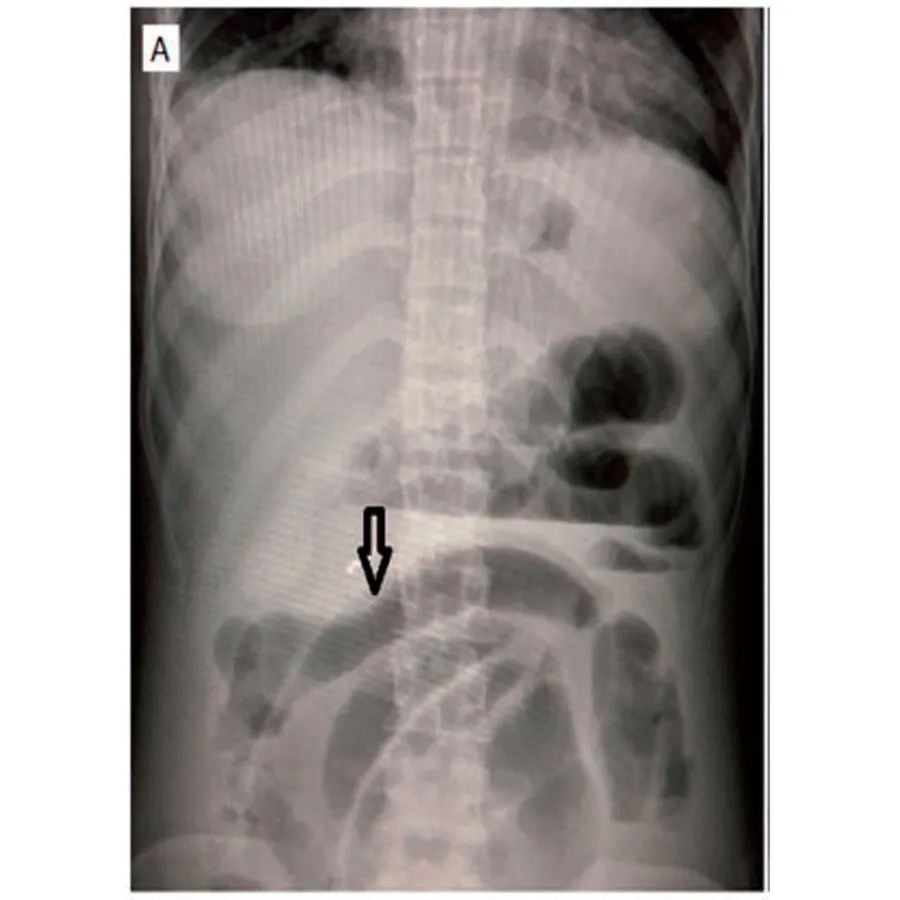

腹部X光片显示肠管扩张(图1A)。

腹部CT下正常人的肠管壁厚度不超过3mm,大于等于4mm则被认为肠管壁异常增厚。常见的CT表现包括肠壁局部或弥漫性增厚,肠壁异常强化,肠管呈梳状排列(梳状征),腹水及肠壁肿大。肠壁增厚通常是多灶性的,不局限于单个血管领域,因为肠系膜血管炎可能同时影响多条血管。增强CT(CTA)扫描清晰显示肠壁和腹部血管,提髙诊断的准确性。腹部增强CT肠管异常可表现为受累增厚肠段的黏膜层和浆膜层出现明显强化,而中间的肌肉层强化较低,犹如一个靶子,故称为“靶形征”或“双晕征”。肠系膜异常表现为肠系膜的血管增粗、增多,异常排列如“梳状”或“栅栏状这是系统性红斑狼疮合并肠系膜血管炎的常见征象。但需要注意的是,机械性肠梗阻,急性胰腺炎等也可引起肠管扩张,肠壁水肿增厚等变化,因此腹部B超,腹部站立位平片,腹部CT不仅可以帮助诊断,同时对于鉴别诊断也非常重要。与普通CT相比,肠道血管CT造影是诊断系统性红斑狼疮合并肠系膜血管炎的金标准,特别是当患者出现肠缺血、血栓等血管炎表现时,CT造影显示肠道节段性改变,正常肠道和异常肠段交替出现,呈多灶性的特征。